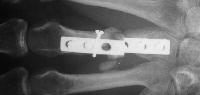

The plate was removed, and the fracture was replated, using more bone graft and larger screws. This plate  held for five months, then also broke. Additionally, a cross union to the ring metacarpal can be seen:

I used the Synthes modular hand set, which has screw intervals different than the small fragment set.

This was the longest plate available, not optimum, but had six cortex purchase on each side of the graft.